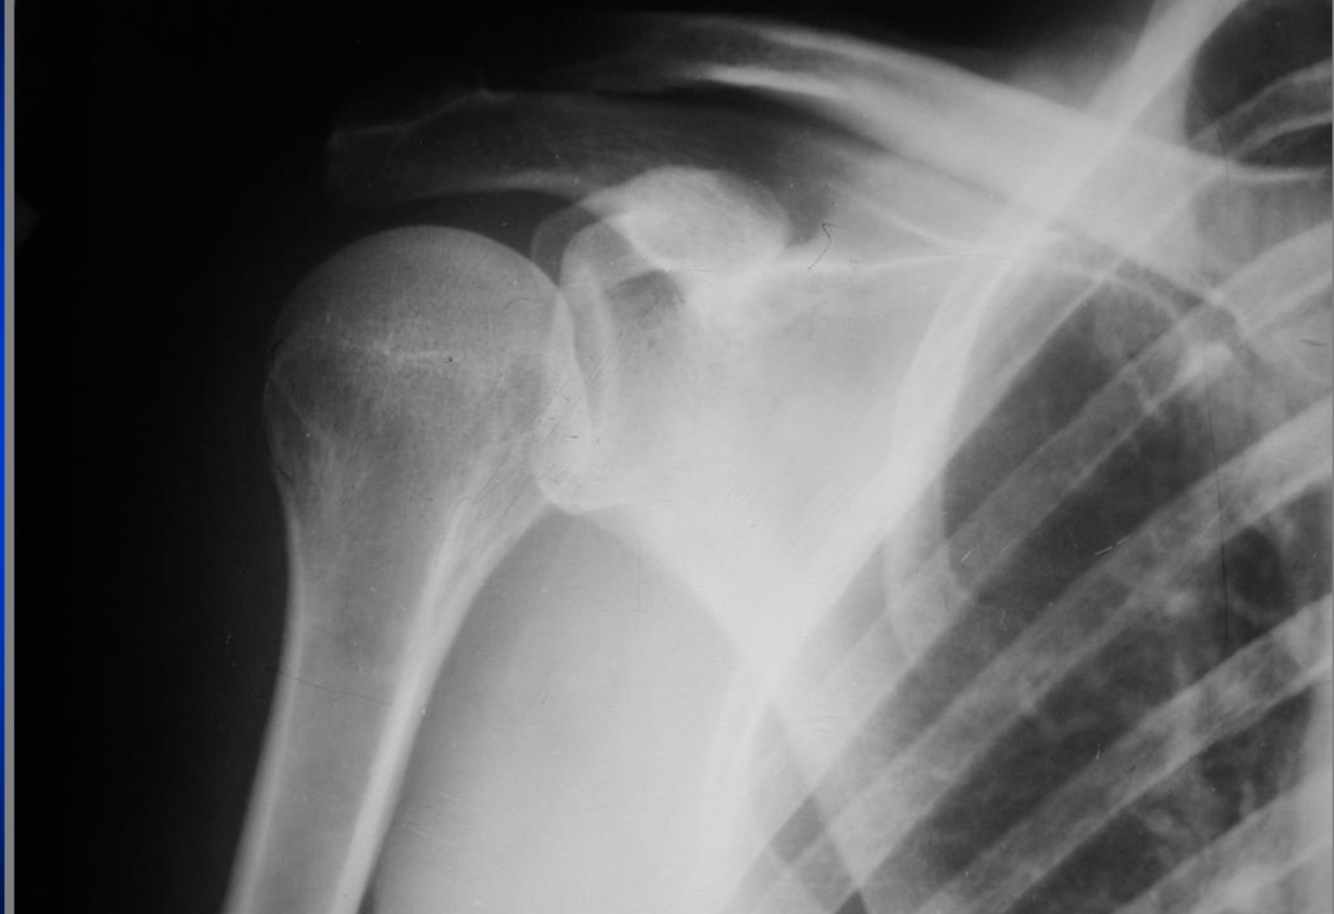

AP Internal Rotation - Shoulder

rotation int car le trochin médiale et tochiter plus lat

rot int de l”paule G car trochin et trochiter sont écarté

positionnnement articulation gléno huméral visible

B technique ok et desité ok

on voit le processus coracoide G

épine

acrominon

glénoide G

cartilage :

glénoidal ou scapulo huméral

acromioclaviculaire